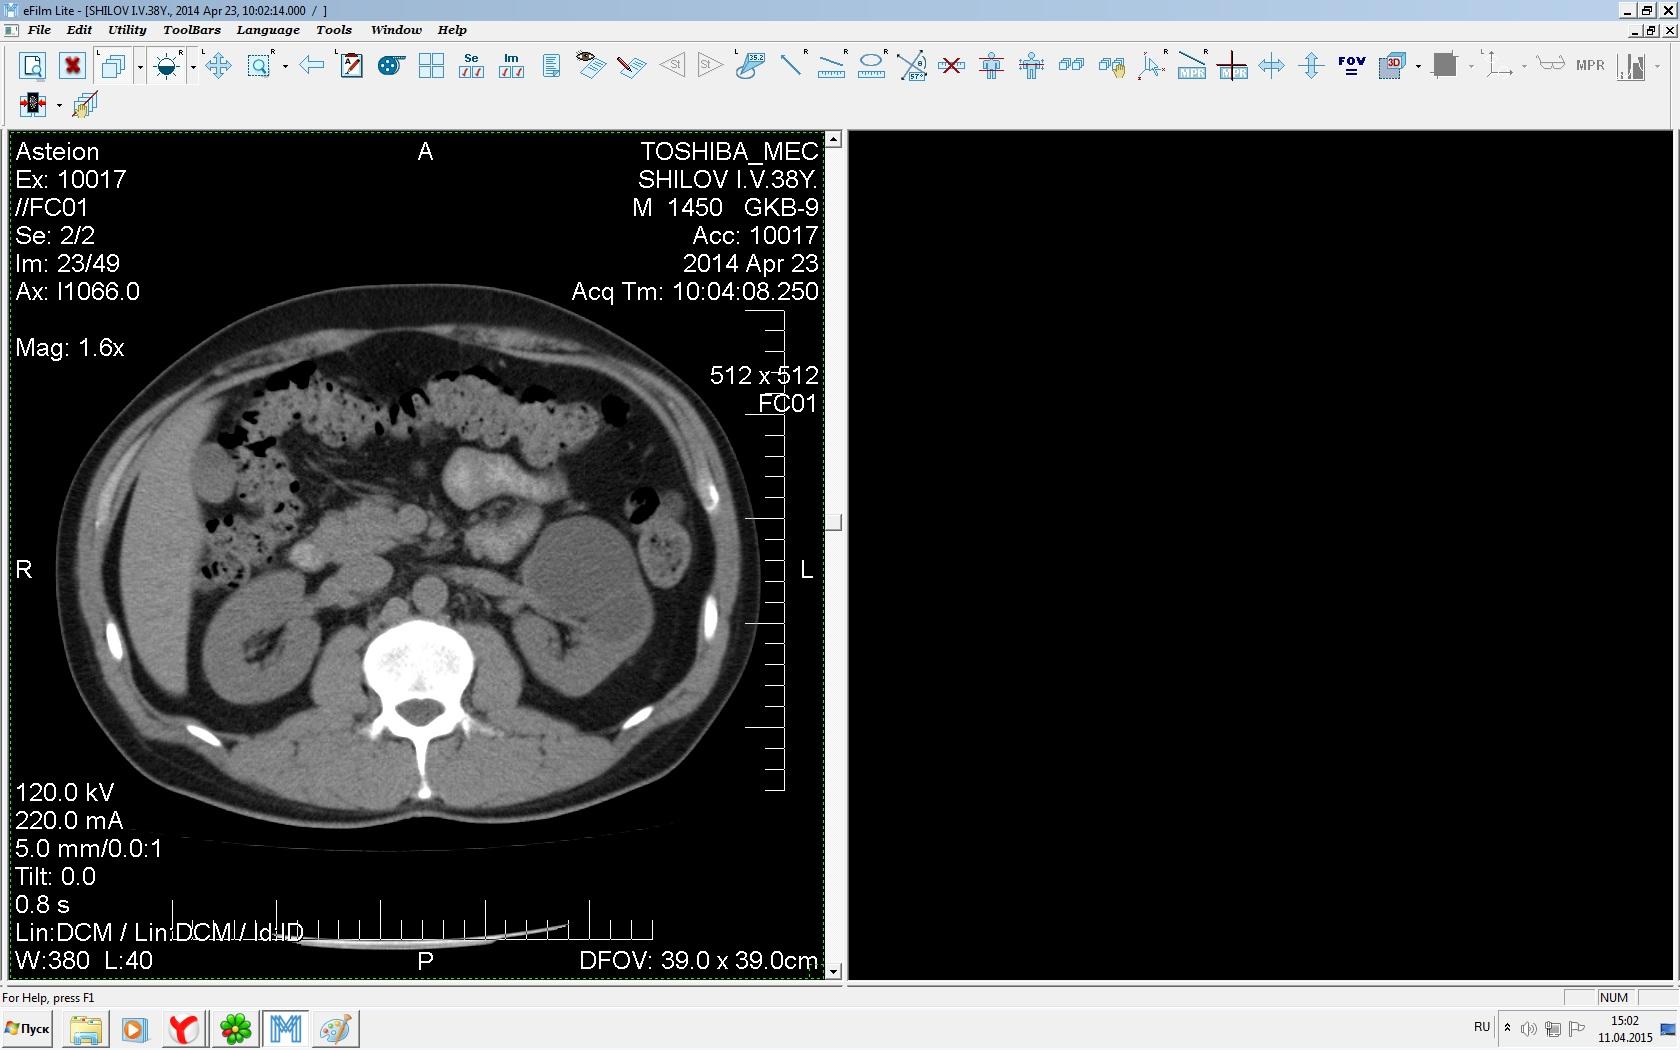

Здравствуйте. У меня киста левой почки. Из заключения: левая почка увеличена, деформирована за счёт наличия в среднем сегменте округлого жидкостного +6, +15 HU образования 66х53 мм, деформирует, поддавливает чаше-лоханочную систему. Сосудистые ножки структурные. В урологии мне сперва предложили лапароскопию, когда я лёг на операцию - изменили на полостную в связи со сложностью. Потом сказали что шансов вырезать кисту без почки практически нет. Даже если кисту удалить чудесным способом, то почка всё равно сложится и не будет работать. В итоге операцию отменили. Скажите, пожалуйста, есть ли современный метод удалить кисту и сохранить почку в моём случае? Томография почки в приложениях. Заранее благодарю.

Эту кисту можно просто пропунктировать, аспирировать и склерозировать - под местной анестезией. Ничего сверхестетственного не определяется по данным КТ. Можете написать мне на почту. aristova-tatyana@mail.ru